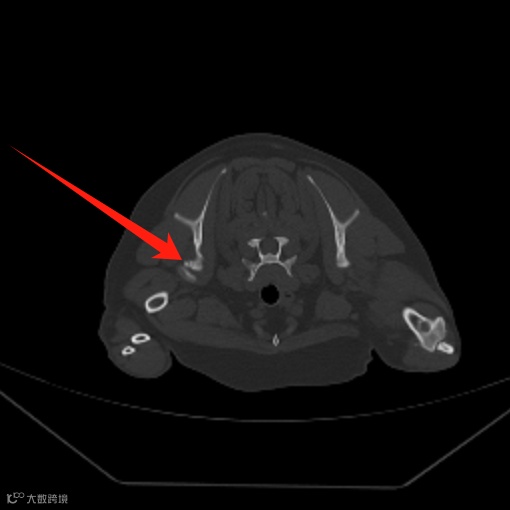

上、下颌联合骨折。